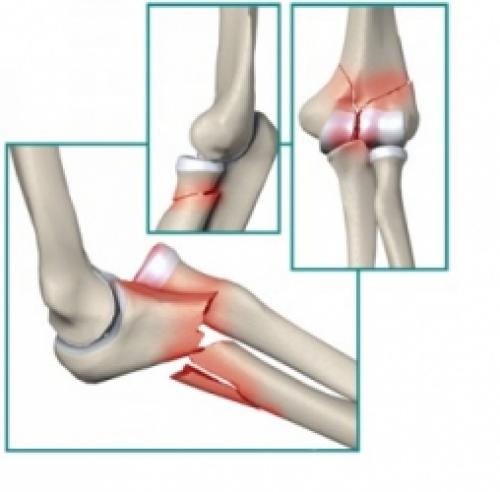

Травмы локтевого сустава в дзюдо. Острые травмы локтя

Переломы:

Костей в суставе три и основных видов переломов тоже три: нижней части плечевой кости, головки лучевой кости и отростка (олекранон) локтевой кости:

Механизм возникновения всех этих переломов одинаков: либо неудачное падение (часто на вытянутую руку), либо удар по локтю, либо(в борьбе)-переразгибание локтя против анатомического сгиба.

Симптомы тоже очень похожи:очевидная деформация над суставом,чрезвычайная боль, усиливающаяся при попытке движения в локте, опухоль, гематома.